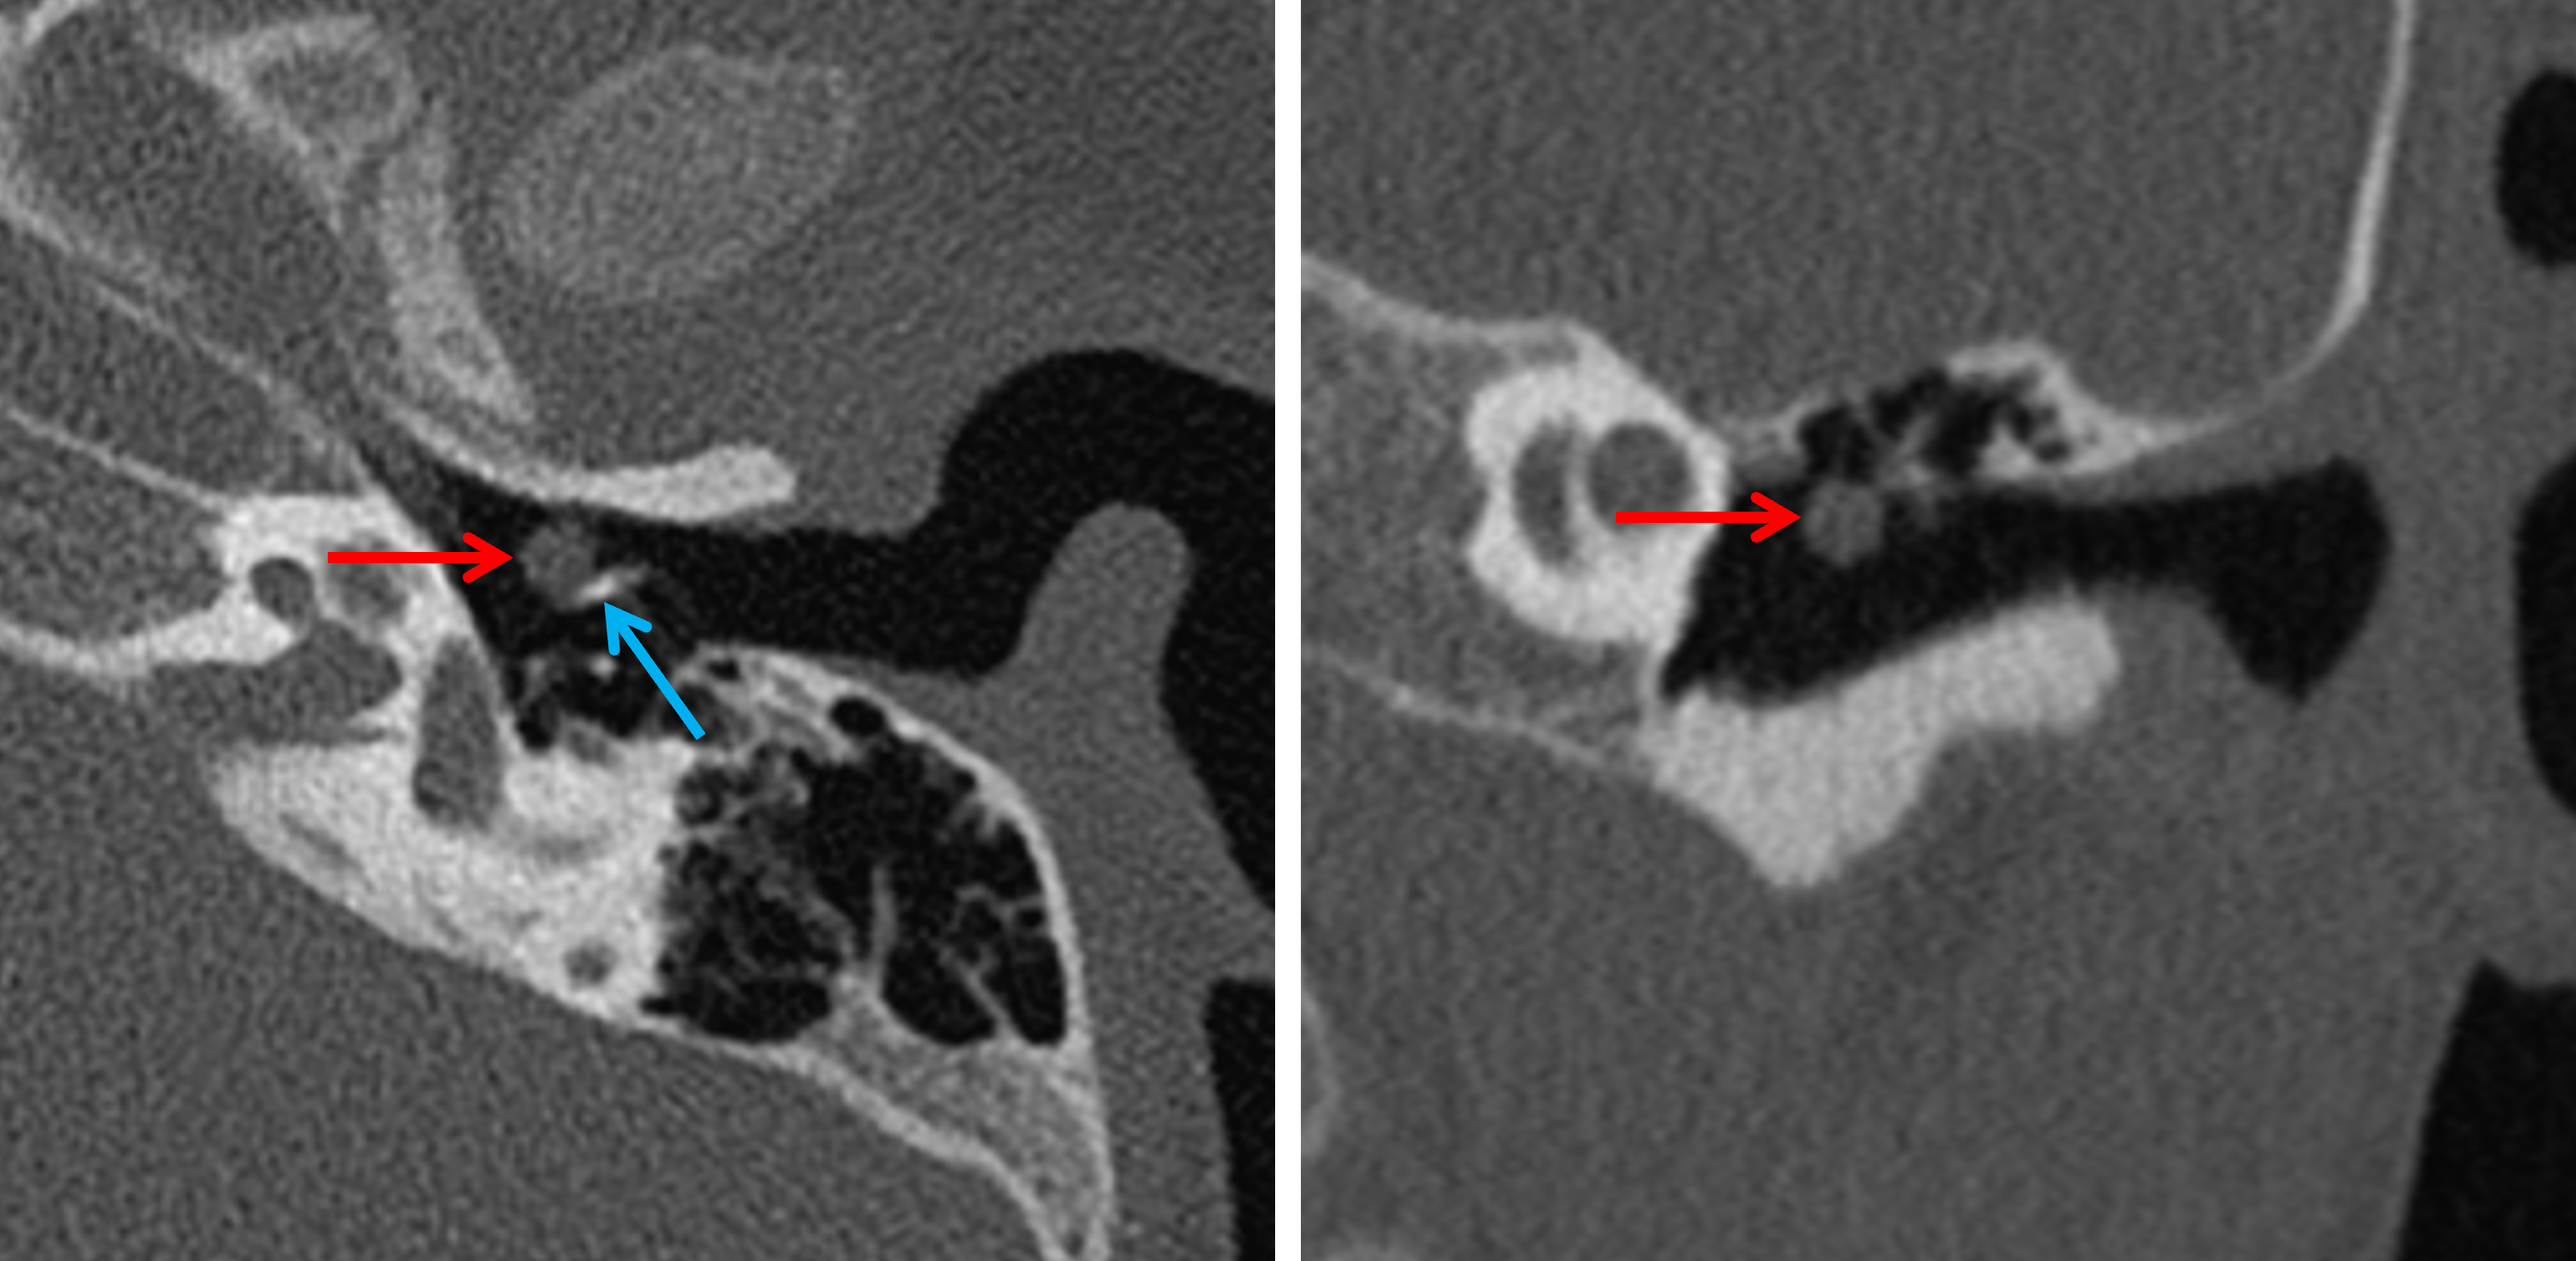

Age: 2

Sex: Male

Indication: Left-sided conductive hearing loss

Congenital cholesteatoma